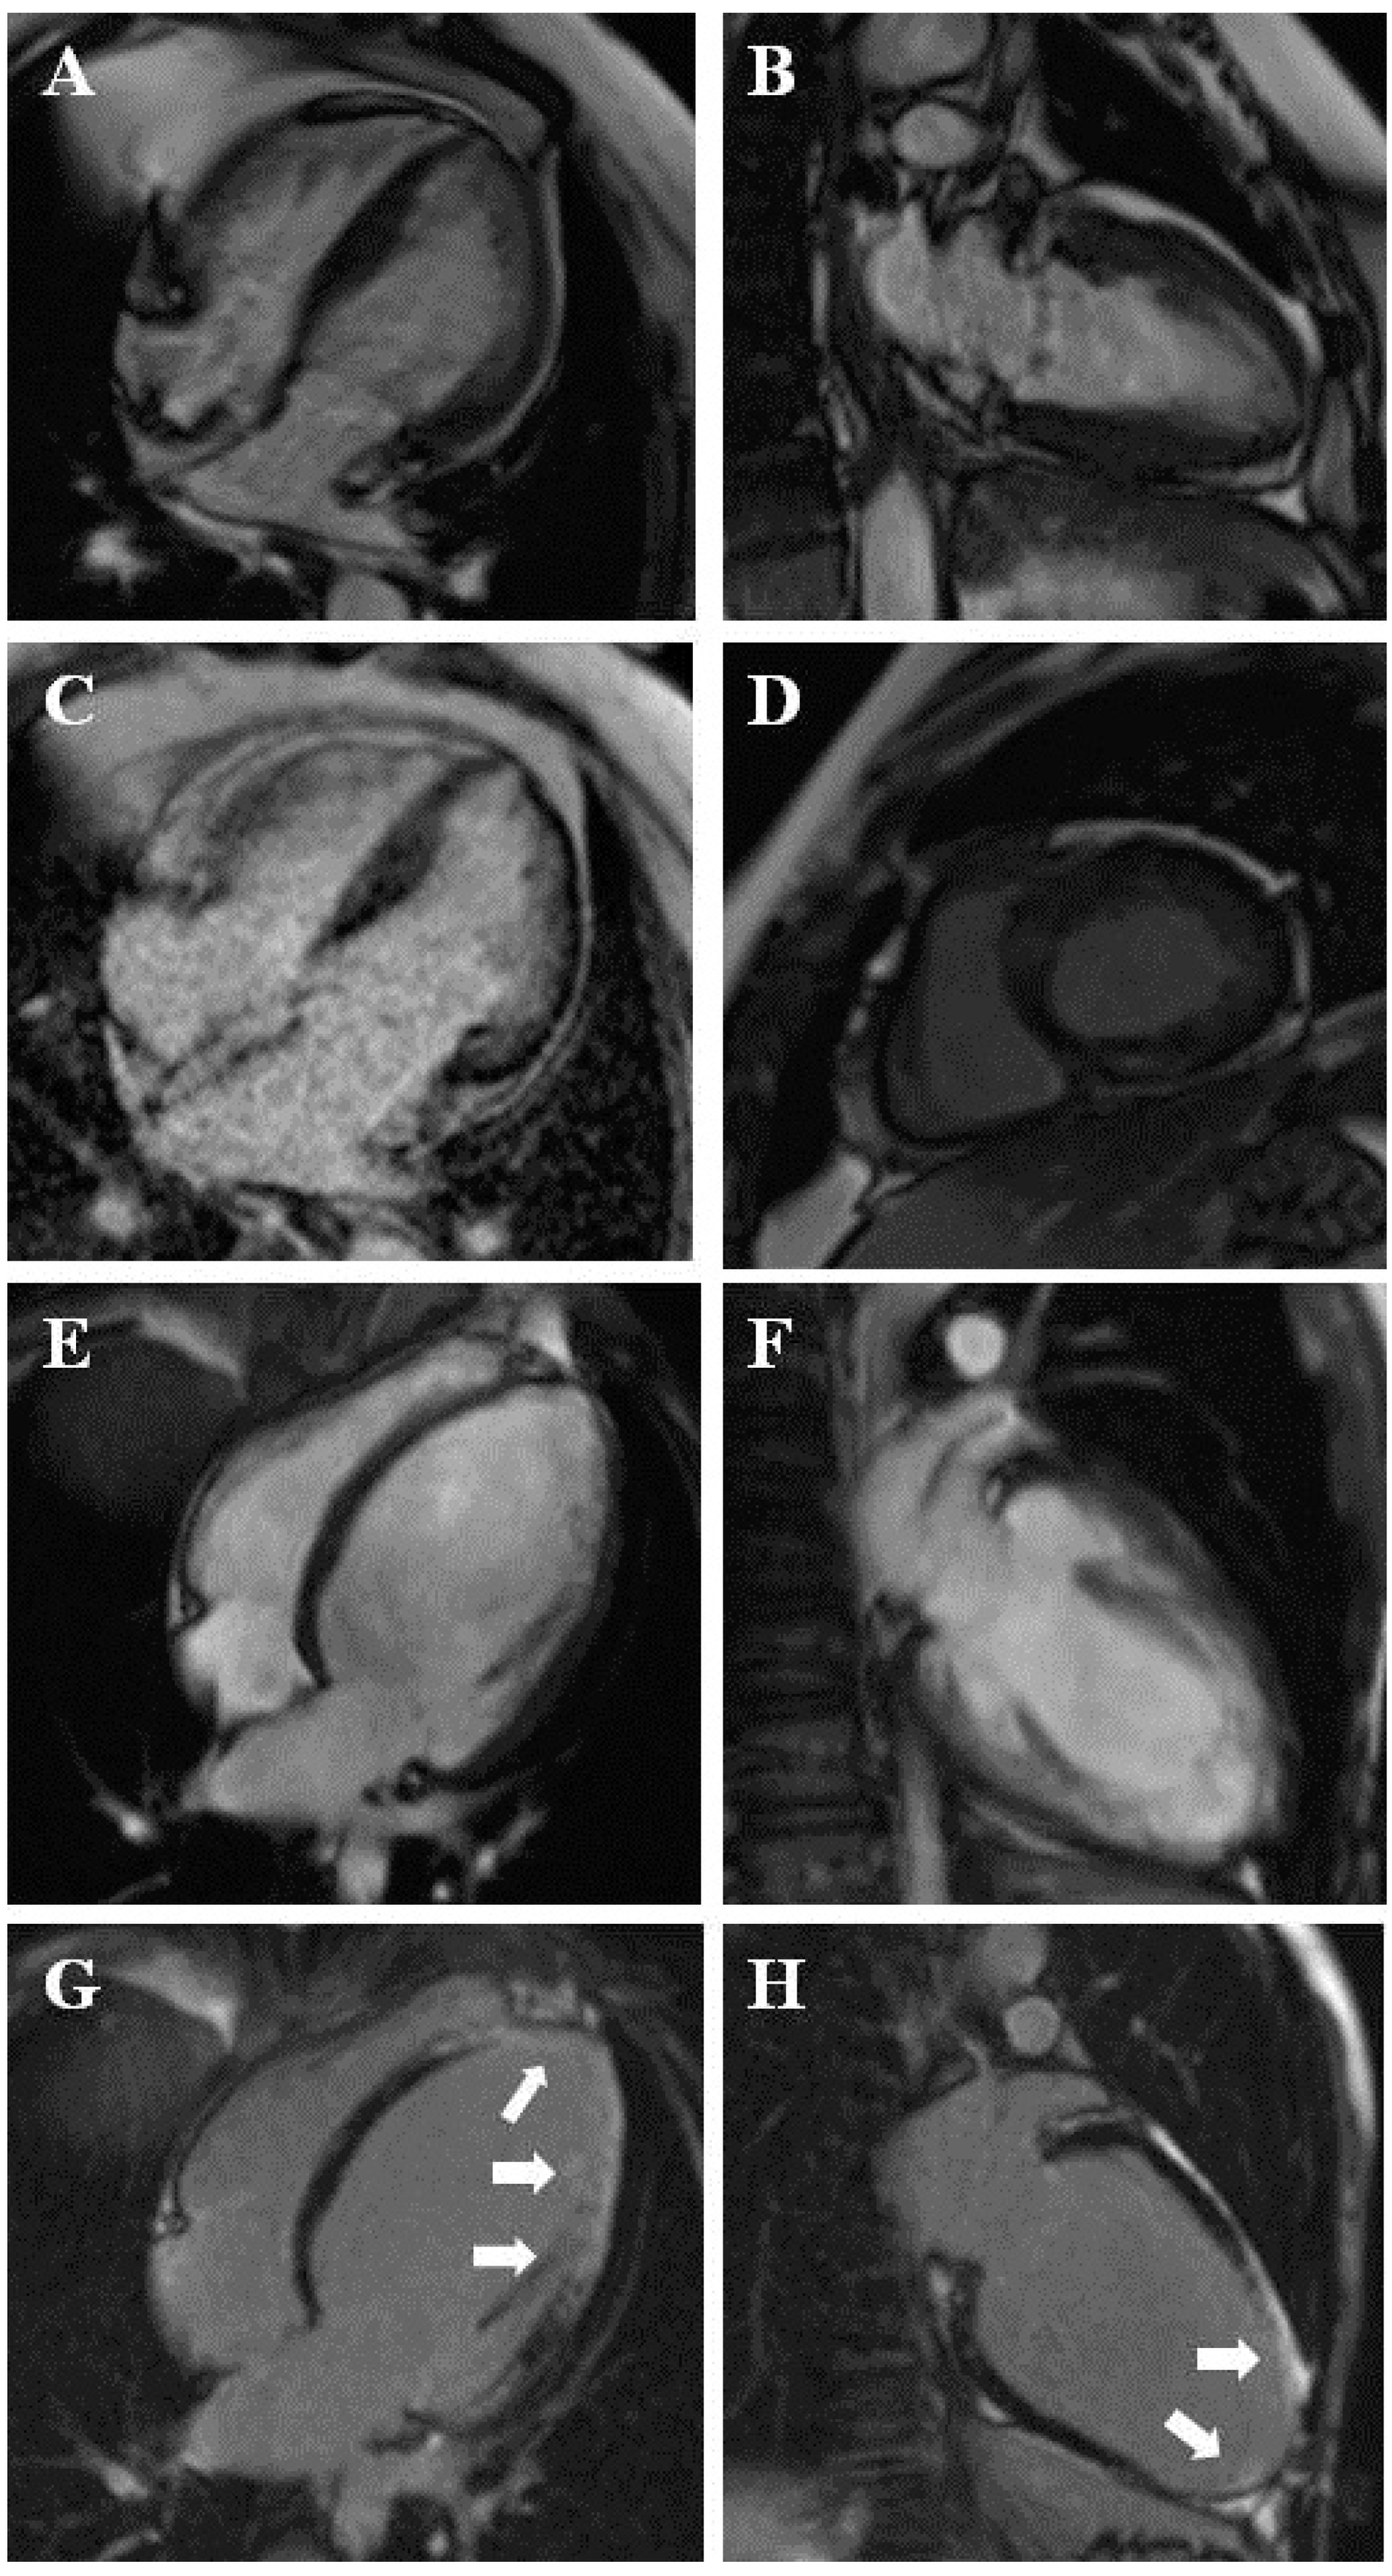

Figure 1.

(A–D) Hypertrophic cardiomyopathy, with LGE in hypertrophied segments (C,D). (E–H) Coronary heart disease with a secondary myocardial trabeculation, with subendocaridal to transmural LGE in basal inferolateral, mid-inferolateral, mid-anterolateral, apical segments, and the apex (arrows) (G,H).

In four (1.5%) patients with suspected LVNC, myocardial trabeculation was a secondary result of dilatation due to coronary heart disease (Figure 1E–H).